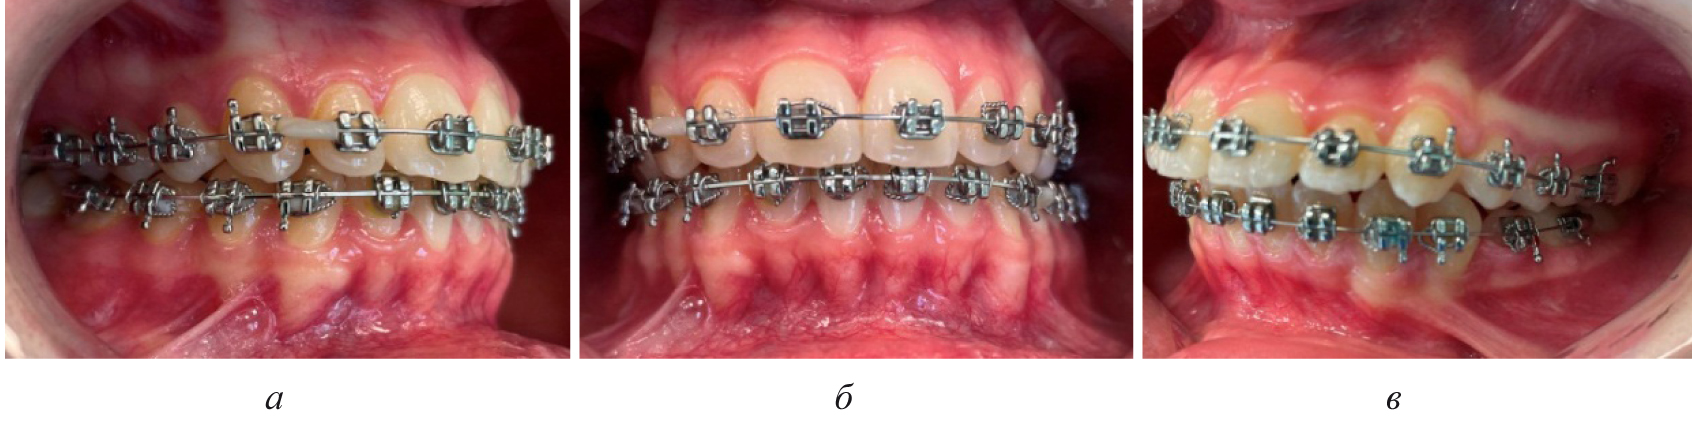

На первом этапе проводилось раскрытие пространства в области ретенированного зуба и создания условий для его прорезывания. После этого устанавливались элементы аппарата на противоположной челюсти (рис. 4).

Последующие этапы ортодонтического лечения техникой эджуайс проводились с учетом общепринятого протокола и этапности смены металлических дуг, что способствовало нормализации окклюзионных взаимоотношений (рис. 5).

Рис. 5. Окклюзионные взаимоотношения справа (а), спереди (б) и слева (в) на завершающем этапе лечения